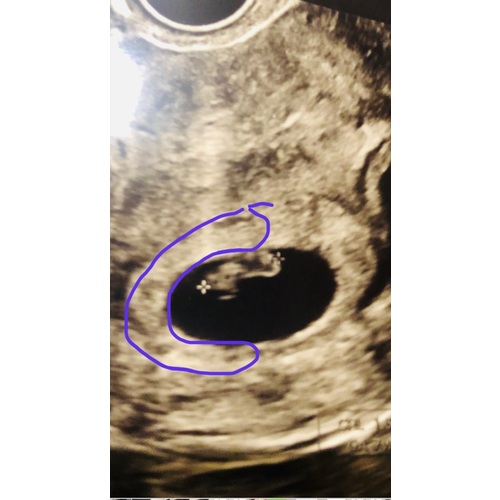

Hier is hij !

Inwendig 馃挅

Uitwendig 馃挋

Heeft te maken met spiegelbeeld in of uitwendig xxx